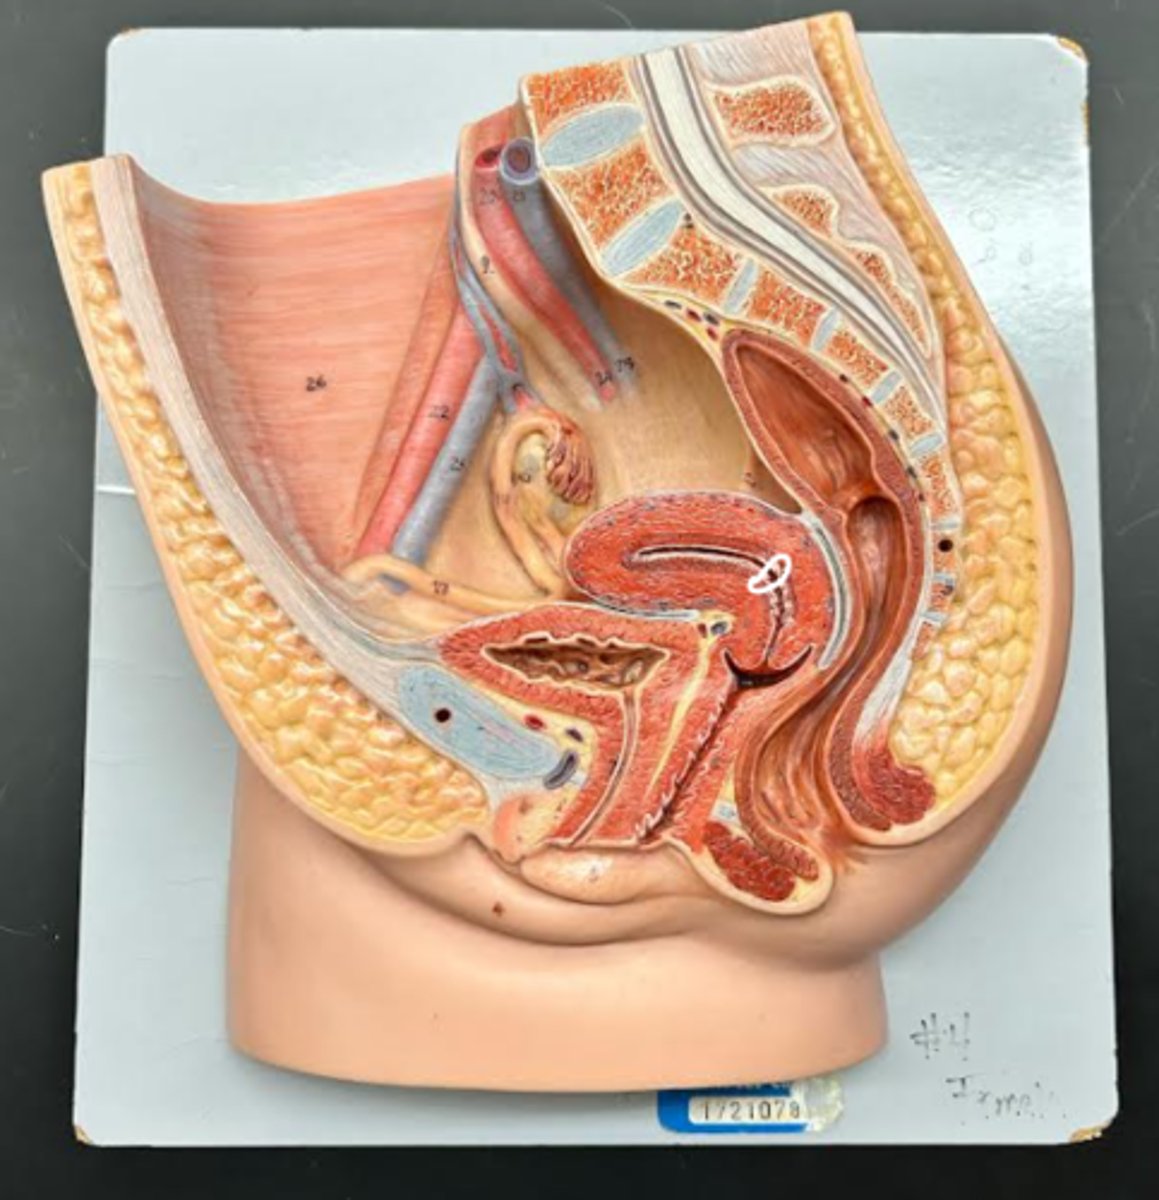

Chapter 29 Anat Phys: Female Reproductive System

Vagina

Vaginal orifice

Hymen

Vaginal fornix

Ovary

Fallopian tube

Fimbriae

Infundibulum

Ampulla

Isthmus

Uterus

Perimetrium

Myometrium

Endometrium

Fundus

Body of uterus

Cervix

Internal os

Cervical canal

External os

Labia majora

Labia minora

Prepuce

Vestibule

Clitoris

External urethral orifice